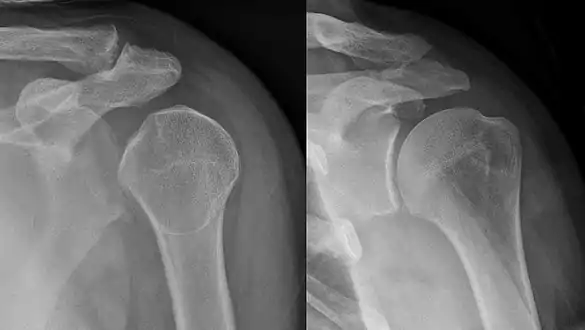

- Dislocated shoulder

- Shoulder dislocations account for 45% of all dislocation visits to the emergency room.[24] Anterior shoulder dislocation, the most common type of shoulder dislocation (96-98% of the time) occurs when the arm is in external rotation and abduction (away from the body) produces a force that displaces the humeral head anteriorly and downwardly.[24] Vessel and nerve injuries during a shoulder dislocation is rare, but can cause many impairments and requires a longer recovery process.[24] There is a 39% average rate of recurrence of anterior shoulder dislocation, with age, sex, hyperlaxity and greater tuberosity fractures being the key risk factors.[25]

Shoulder dislocation before (left) and after (right) being reduced